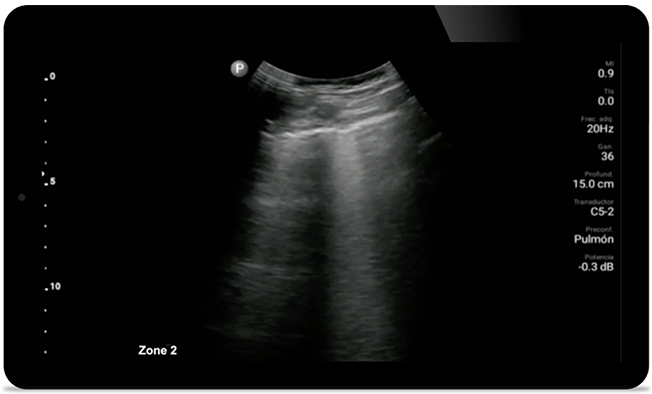

Keep an eye on COVID pneumonia

Keep an eye on COVID

pneumonia

Lumify can help give results similar to a chest CT when evaluating pneumonia and adult respiratory distress syndrome.